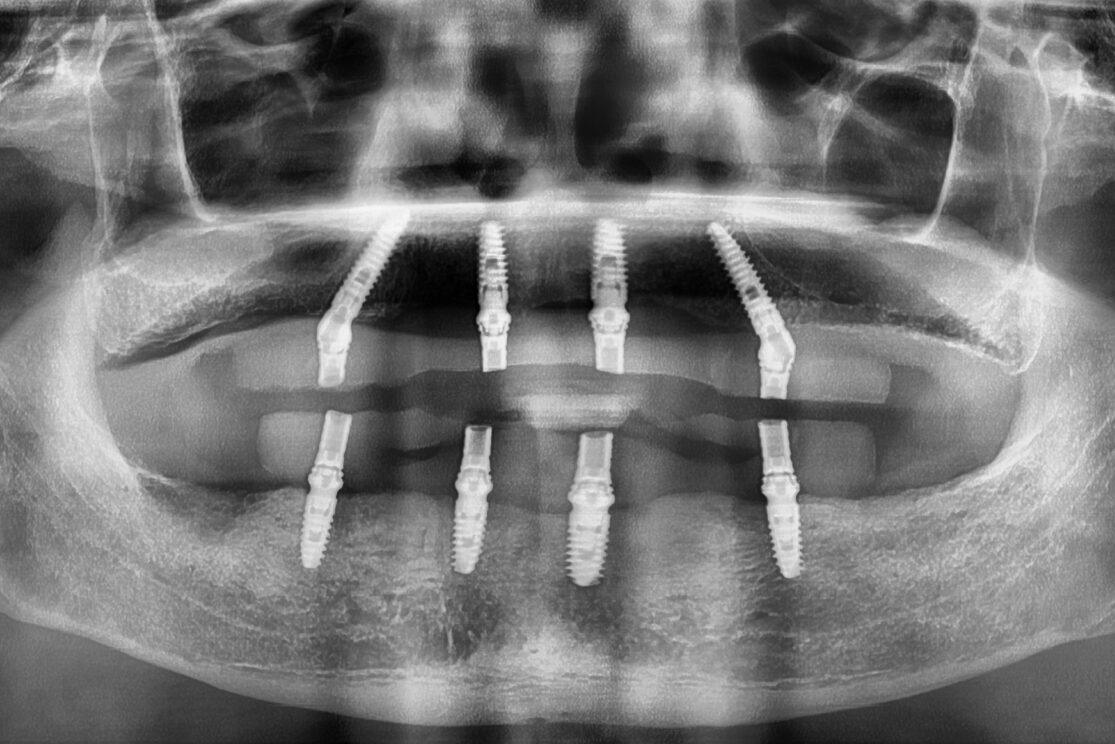

金門客人全口重建

【醫師見證】 來自金門的廟公,走過千里找回笑容與尊嚴的全口重建之路 在我執業多年的牙醫生涯中,見過許多患者從不同地方來到診所,但這位來自金門的師父,讓我特別感動。 金門客人全口重建以後,整個外觀看不出…

全口All on 4

2017第一例All on 4